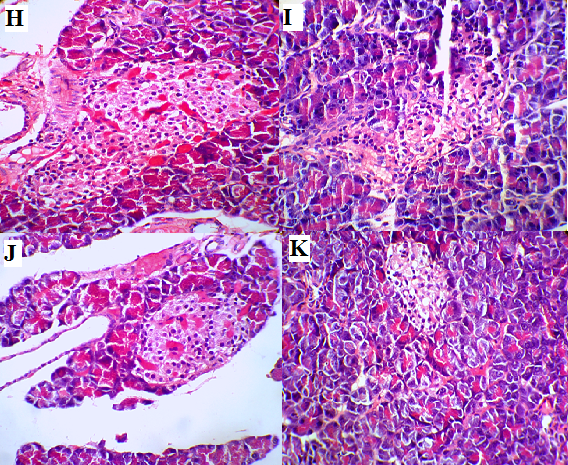

Histological observation of pancreatic sections from healthy control rats showed normal distribution of the islets of Langerhans consisting of beta and non-beta cells with predominant exocrine pancreatic tissue which composed of acini with draining ductless. The endocrine portions were found as well capsulated scattered nodules imgded within the acinar portion appeared lightly stained than the surrounding acinar cells, with intact interlobular connective tissue and interlobular duct. Each islet consisted of faintly stained polygonal cells of beta and non-beta cells arranged in cords separated by a network of blood capillaries. T2DR sections showed severe pathological changes of pyknosis, karryorexis, karryolysis and vaculation in both glandular and acinar portion. The pancreas of T2DR enriched with multi-strain probiotics showing moderate degenerative and necrotic changes with amyloid accumulation (fig. 2). The pancreas of T2DR received saffron or cardamom or ginger cinnamon or without multi-strain probiotics were noted a variable moderate pathological and degenerative response. The pancreas of T2DR received herbs with multi-strain probiotics were noted a variable slight pathological response (fig. 3).

Fig. 3: Histopathology of pancreatic tissues (HandE.400x). Pancreas of type 2 diabetic rats (T2DR) received saffron (D), cardamom (E), ginger (F), and cinnamon (G) without multi-strain probiotics were noted a variable moderate pathological and degenerative response with some degeneration of the β cell (arrow) that imgded in exocrine portion of pancreas. Pancreas of T2DR received saffron (H), cardamom (I), ginger (J), and cinnamon (K) with multi-strain probiotics were noted slight pathological response with normal size islets cells (arrow)